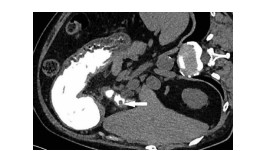

Hepatocellular carcinoma with gastrointestinal stromal tumor: A case report

Xu YANG, Zhengrong SHI

2021, 37(8): 1909-1910. DOI: 10.3969/j.issn.1001-5256.2021.08.033

Abstract(880) HTML (269) PDF (2171KB)(64)

Abstract: